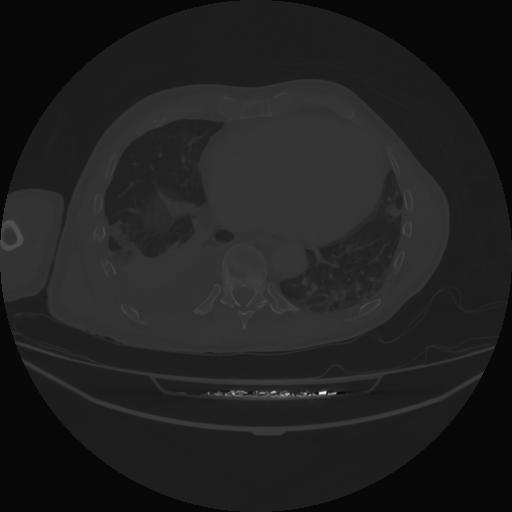

5 CUERPO,CE,Vol,1.0,CUERPO,,